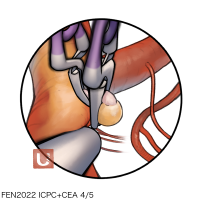

FEN2022シリーズ